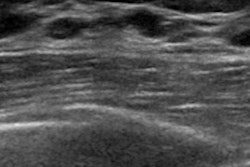

The 16 hyperechogenic breast cancers represented 1.5% of all the malignancies in the series. The women with these cancers ranged in age from 42 to 81 with a median tumor size of 26 mm. On ultrasound, three of these lesions appeared to be low-risk, while the majority of the lesions appeared to be very suspicious, especially when extrapolating the echogenicity due to margin and shapes.

Smaller tumors presented with small, central hypoechogenic foci. Larger tumors presented with a mixture of small hypoechogenic areas among extensive hyperechogenic areas.

"Another remarkable characteristic is the presence of surrounding hypoechogenic adipose tissue in almost all the lesions," Castillo Balladarez said.

The main characteristic that gives malignant breast lesions hyperechogenicity is the presence of adipose tissue mixing with tumoral cells -- most of the time it is surrounded by hypoechoic fat tissues.